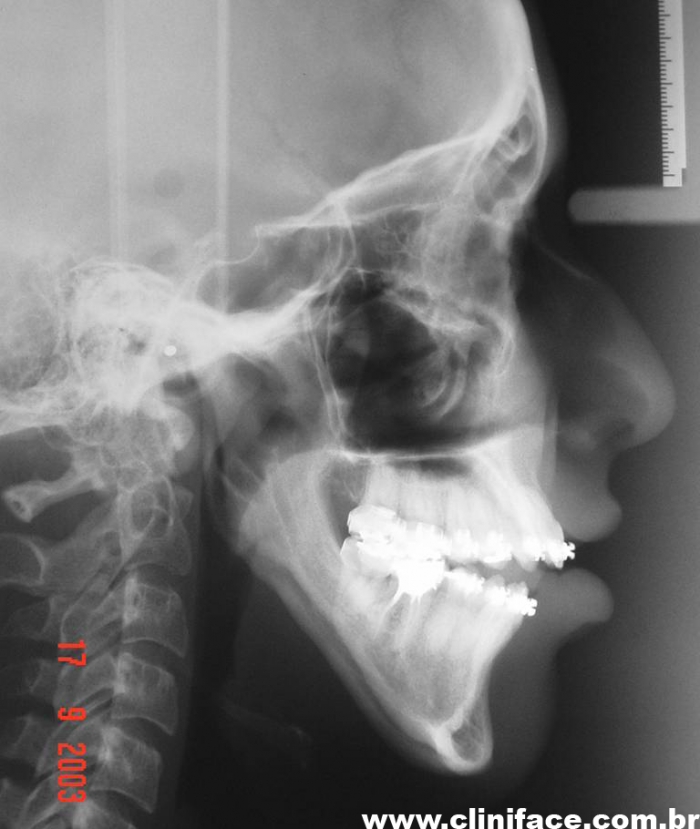

Telerradiografia final